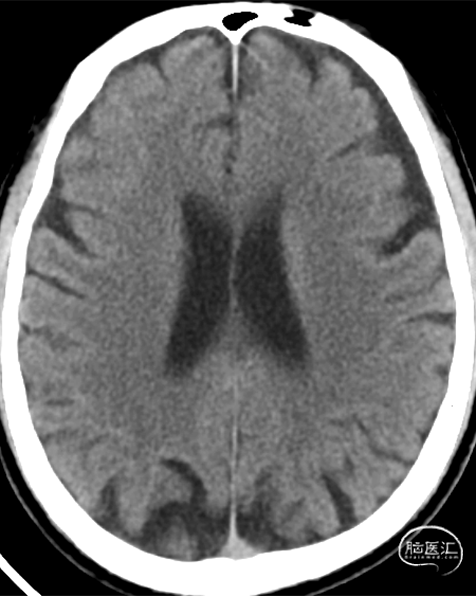

➢ 颅脑CT(平扫)

1.左侧顶叶、右侧丘脑、双侧基底节区及侧脑室旁多发腔梗灶,脑萎缩。

2.双侧上颌窦炎。